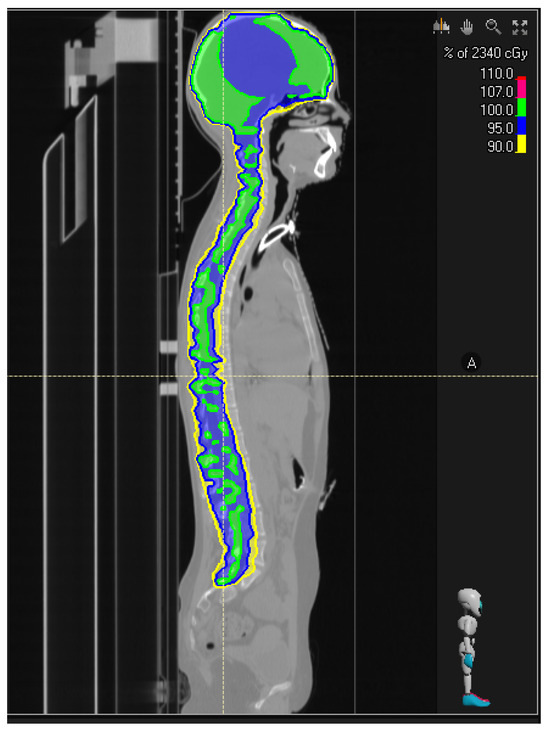

5. Radiotherapy for Local or Disseminated Disease

- Perez-Somarriba, M.; Santa-Maria, V.; Cruz, O.; Muchart, J.; Lavarino, C.; Mico, S.; La Madrid, A.M. Craniospinal irradiation as a salvage treatment for metastatic relapsed DIPG. Pediatr. Blood Cancer 2020, 68, e28762. [Google Scholar] [CrossRef]

- Massimino, M.; Biassoni, V.; Mastronuzzi, A.; Schiavello, E.; Barretta, F.; Quaglietta, L.; Milanaccio, C.; Pecori, E.; Cacchione, A.; Di Ruscio, V.; et al. DIPG-04. The Benefit of Craniospinal Irradiation (csi) Rescue in Phase 2 Randomized Study of Radiotherapy (rt), Concomitant Nimotuzumab and Vinorelbine and Re-Irradiation at Relapse, Versus Multiple Elective Radiotherapy Courses with Concomitant Vinorelbine and Nimotuzumab for Newly Diagnosed Childhood and Adolescence Diffuse Intrinsic Pontine Glioma (dipg). Neuro-Oncology 2024, 26. [Google Scholar] [CrossRef]